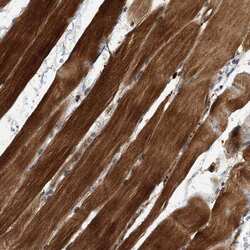

PA5-56091 IHC

Method: